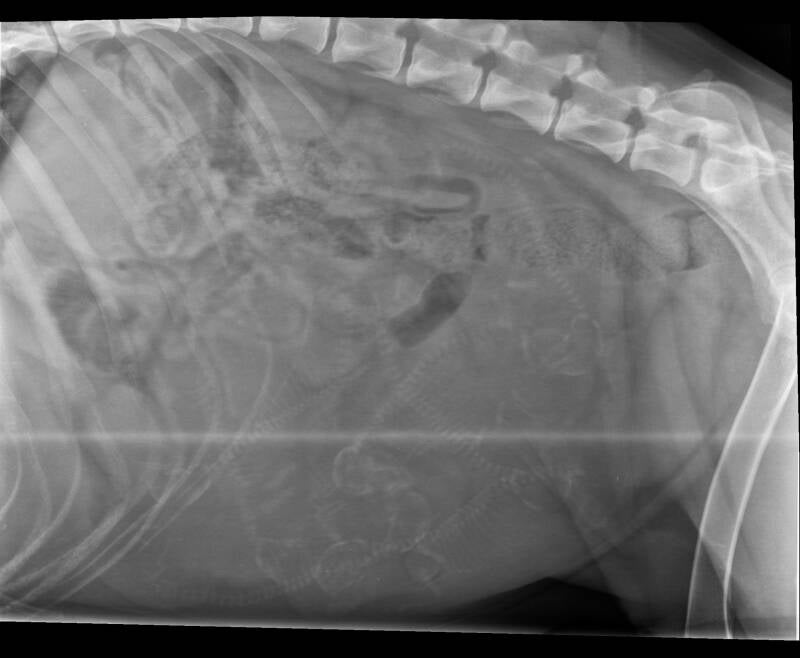

Röntgenfoto

Vandaag (25 januari) gingen we met Norah nog een keer naar de dierenarts, dit keer voor de röntgenfoto. Op de röntgenfoto kunnen we zien hoeveel pups Norah ongeveer krijgt. Hoeveel pups telt u? ;)